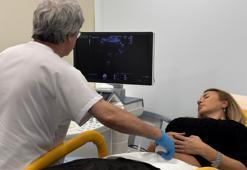

‘Her 4 kadından birinde düşük yumurtalık rezervi görülüyor’Kariyer ve evlilik planlarının ertelenmesiyle kadınlarda anne olma yaşının yükseldiğini belirten Kadın Hastalıkları ve Doğum Uzmanı Prof. Dr. Murat Ekin, doğurganlığı doğrudan etkileyen yumurtalık rezervi düşüklüğü konusunda uyarılarda bulundu. Prof. Dr. Ekin, “Yumurtalık rezervini belirleyen en önemli faktör yaştır. 20’li ve 30’lu yaşlarda en yüksek seviyededir, 30’dan sonra azalmaya başlar ve 35 yaş sonrası bu düşüş hızlanır. Düşük over rezervi neredeyse her 4 kadından birinde karşımıza çıkabiliyor" dedi.

‘Endometrioziste klinik tanı ile tedavi hızlanabilir’Kadın Hastalıkları, Doğum ve Tüp Bebek Uzmanı Doç. Dr. Funda Göde, “Endometriozis, tanısı en sık geciken hastalıklardan biri ve bu gecikme ortalama 4 ila 11 yılı bulabiliyor. Amerikan Kadın Hastalıkları ve Doğum Uzmanları Koleji’nin (ACOG) Mart 2026’da yayımladığı yeni kılavuz, bu uzun bekleyişe neden olan tanı yaklaşımını yeniden ele alıyor. Kılavuza göre, her hastada kesin tanı için ameliyat beklemek gerekmeyebilir, uygun durumlarda klinik değerlendirmeyle tedaviye daha erken başlanabilir” dedi.

‘Kadınlarda şiddetli adet ağrısının nedeni ‘çikolata kisti’ olabilir’Çikolata kistinin çoğu zaman şiddetli adet ağrılarıyla kendini gösterdiğini belirten Biruni Üniversitesi Tıp Fakültesi Hastanesi Kadın Hastalıkları ve Doğum Uzmanı Dr. Öğr. Üyesi Fulya Özkal Molla, erken tanının önemine değindi.

‘Endometriozis kadınların yüzde 10'unu etkiliyor’ENDOMETRİOZİSİN rahim iç tabakasını (endometrium) oluşturan dokunun rahim dışında, genellikle pelvis bölgesindeki diğer organlarda yerleşmesi olarak tanımlandığını belirten Kadın Hastalıkları ve Doğum Uzmanı Op. Dr. Ömer İlker Göçmen, “Bu durum üreme çağındaki kadınların yaklaşık yüzde 10'unu etkiliyor ve yaygın bir şekilde görülüyor” dedi.